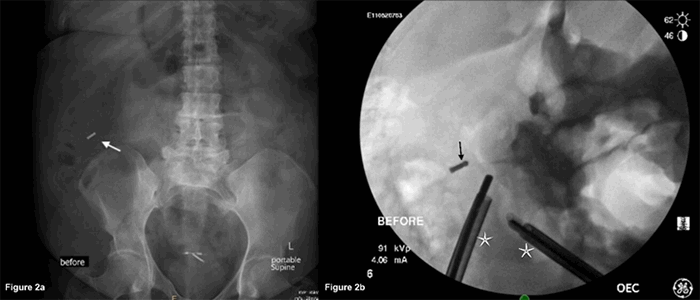

This procedure was followed by a repeat manual count, which again confirmed the correct surgical count. A detailed examination of the used cotton gauze demonstrated that an RF tag was missing from the retained gauze as also a small hole in the green cloth used to secure the tag. A portable X ray of the abdomen was obtained, revealing a radiopaque object similar to a tag in the upper-right quadrant (Figure 2A). The pneumoperitoneum was reestablished, the ports were replaced, and standard laparoscopy was initiated. The encapsulated RF tag was not visualized on an initial inspection with a 300 camera. Intraoperative fluoroscopy was then used to localize the tag (Figure 2B). Triangulation with a laparoscopic instrument and intraoperative fluoroscopy revealed the tag in hepatic flexure mesentery (Figure 3). The tag was retrieved, and the count was again confirmed manually and with the RF Assure surgical sponge detection system (Figure 4).

Figure 2. A) Portable on-table abdomen X ray, antero-posterior view. Arrow showing dislodged RF tag in the right upper quadrant. B) Use of intraoperative fluoroscopy to triangulate the precise location of RF tag. Arrow is showing the RF tag and is pointing to surgical instruments.